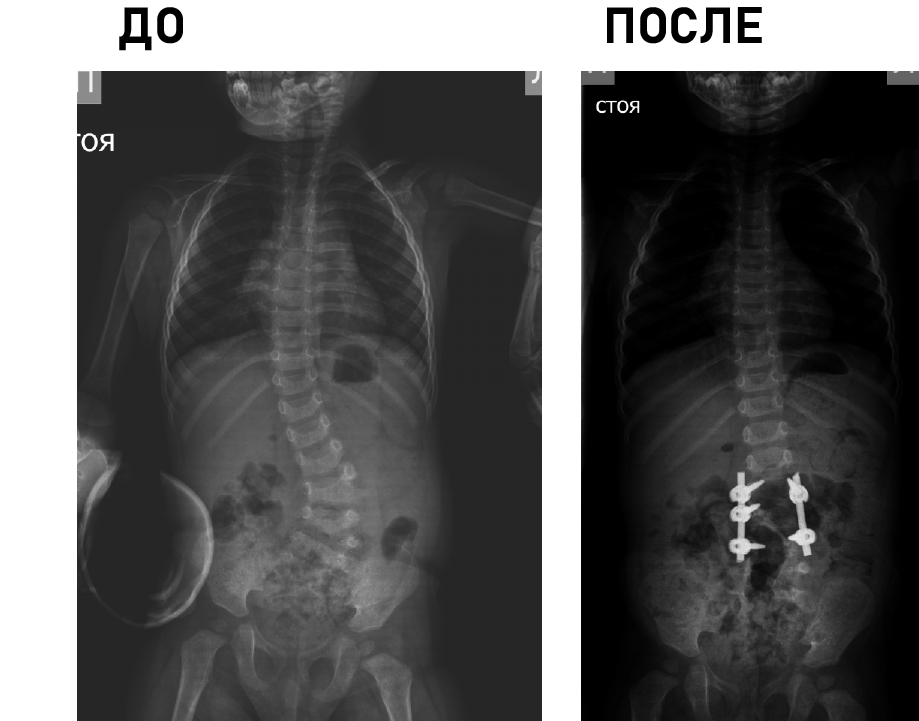

Клиника является единственным медицинским учреждением Российской Федерации, выполняющим полный комплекс диагностических и лечебных мероприятий у детей с деструктивными поражениями любых отделов скелета, в т.ч. малоинвазивные биопсии, иммунологические исследования, гистологическую и бактериологическую верификацию.

Основной принцип работы: обязательный учет возрастных особенностей ребенка и потенциал его роста.

Технические возможности: технологии малоинвазивной (MIS) и реконструктивной хирургии, костнопластические материалы и инструментальная фиксация, современное силовое и ультразвуковое операционное оборудование, навигация, нейромониторинг.